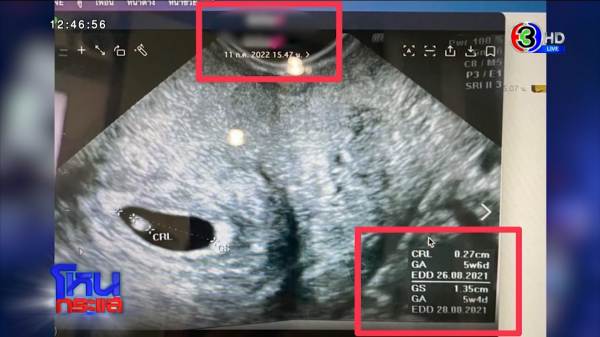

ในไลน์ที่คุณคุยกัน คุณถามว่าวงกลมคือลูกใช่มั้ยครับ คุณชุ่มฉ่ำหัวใจ แต่ชุ่มฉ่ำได้ไม่นาน ข้างล่างอัลตร้าซาวด์ 28 เดือน 8 2021 ก็ไม่เข้าใจว่าไปทำอีท่าไหนไม่ตรงกับภาพข้างบนที่ส่งมา ตอนแรกคุณไม่รู้ข้อมูลข้อเท็จจริง หลังจากเธอส่งอัลตร้าซาวด์มาว่าท้องกับคุณ คุณทำยังไงต่อไป?

ใบอัลตร้าซาวด์ที่ฝ่ายหญิงส่งให้ฝ่ายชาย กรอบข้างล่าง EDD 28.08.21 EDD คือกำหนดการคลอด แสดงว่าอัลตร้าซาวด์อันนี้คลอดไปแล้ว ตั้งแต่วันที่ 21 เดือน 8 ปี 21 จากนั้นคุณทำยังไง ที่เขาให้จดทะเบียน คุณก็จด?

หลังจากนั้นพีคในพีค ผู้หญิงที่คุณจดทะเบียนด้วย มีผัว 3 คนเป็นตัวเป็นตน ลูกอีก 4 ไม่รวมผู้เสียหายคนอื่น ๆ อีก แสดงว่าอัลตร้าซาวด์ที่เขาส่งมาให้คุณ น่าจะเป็นอะไร?

มาร์ช : น่าจะเป็นของลูกคนที่ 4

อัลตร้าซาวด์เป็นของเธอจริง ๆ แต่เป็นท้องที่เกิดกับสามีคนก่อน และเป็นลูกคนที่ 4 ของเธอ และเอามาหลอก พอคุณไปตรวจสอบ ได้ไปติดตามอีกมั้ย?